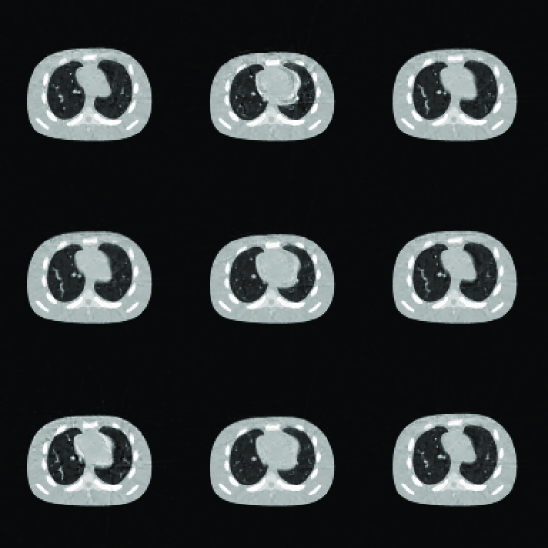

3.2 Noisy data

For the case with noise in the projection data, the parameter K𝐾K is selected as K=4𝐾4K=4 according to Figure 5. Figure 6(a) depicts the reconstructed images. The relative error of the restored cine-CBCT images is 6.81%percent6.816.81\%. The columns of 𝑳𝑳\bm{L} and the rows of 𝑹𝑹\bm{R} are plotted in Figure 6(b) and (c), respectively. Again, we see that the columns of 𝑳𝑳\bm{L} are meaningful basis corresponding to the average image as well as the variations between them, and the rows of 𝑹𝑹\bm{R} oscillate periodically.

Refer to caption

(a) The restored cine-CBCT image with the relative error 6.81%percent6.816.81\%. From left to right, top to bottom: frame 40,80,,360408036040,80,\ldots,360.

Figure 6: Result of cine-CBCT image reconstruction with noise at 0.5 mAs/projection.